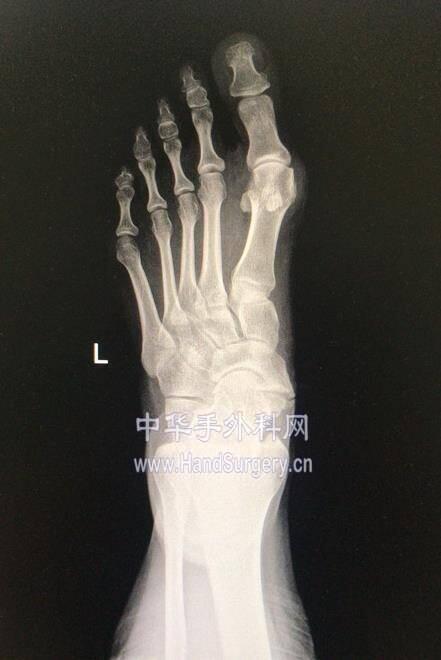

微信图片编辑_20191218175444.jpg 两侧均为中度